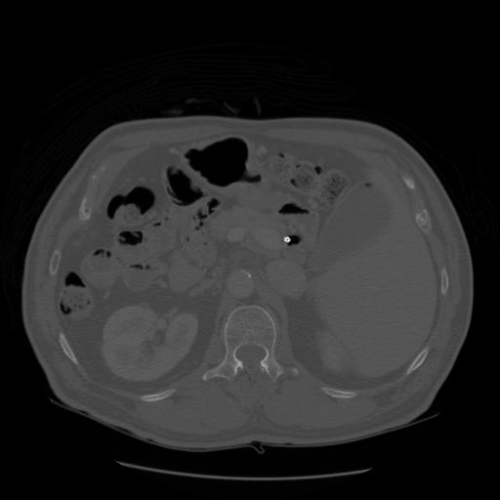

As shown in Fig. 2, we ensure that contrast enhancement is applied dynamically and adapts to each individual image by leveraging the underlying grayscale intensity distribution, rather than imposing uniform adjustments across the entire dataset. The enhanced output is subsequently validated and converted to an 8-bit representation to ensure numerical stability and compatibility with downstream processing. The pipeline supports parallel batch processing with consistent configuration settings, while allowing key parameters, such as the background intensity threshold, percentile bounds for contrast stretching, CLAHE clip limit [48], and tile grid size, to be tuned for specific datasets. Artifact suppression is achieved through smooth histogram redistribution, bilinear interpolation between tiles, and edge-aware processing strategies. This preprocessing design is particularly well suited for low-contrast medical images, especially CT and MRI scans, where preserving subtle anatomical details is essential for reliable diagnosis and accurate segmentation in subsequent deep learning pipelines.

For experimental evaluation, we leveraged three publicly available medical imaging datasets. The FLARE22 dataset [33] served as the primary source for training and validation, while additional samples from the SAROS [40] and CHAOS [25] datasets were incorporated for extended testing and validation. All datasets comprise abdominal CT and MRI scans provided in NIfTI format; however, instead of processing full 3D volumes, we extracted 2D axial slices for analysis. Middle axial slices were selected, as they consistently offer clear visualization of key abdominal organs and representative anatomical context. While FLARE22 forms the core experimental dataset, the inclusion of SAROS and CHAOS enables assessment of the robustness and generalizability of the proposed approach across varying imaging protocols and scanner characteristics.